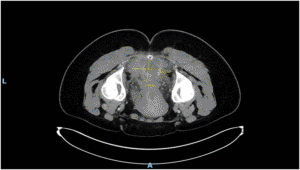

Imaging via MRI and CT demonstrated a complex, encapsulated lesion with peripheral enhancement and restricted diffusion. Multidisciplinary evaluation suggested a congenital epidermoid or duplication cyst. Given the absence of malignancy and surgical complexity, a conservative management strategy was adopted.

Figure 1: Figure 1 Duplication cyst 2025 MRI sagittal plane

Figure 2: Figure 2 Duplication cyst 2025 MRI sagittal plane

Figure 3: Figure 3 Duplication cyst 2020 Coronal plane

Figure 4: Figure 4 Duplication cyst 2020 sagittal plane

Figure 5: Figure 5 Duplication cyst axial 2020 plane post cystic aspiration

Figure 6: Figure 6 Duplication cyst 2025 sagittal plane

Figure 7: Figure 7 Duplication cyst 2025 MRI axial plane

Figure 8: Figure 8 Duplication cyst 2020 axial plane